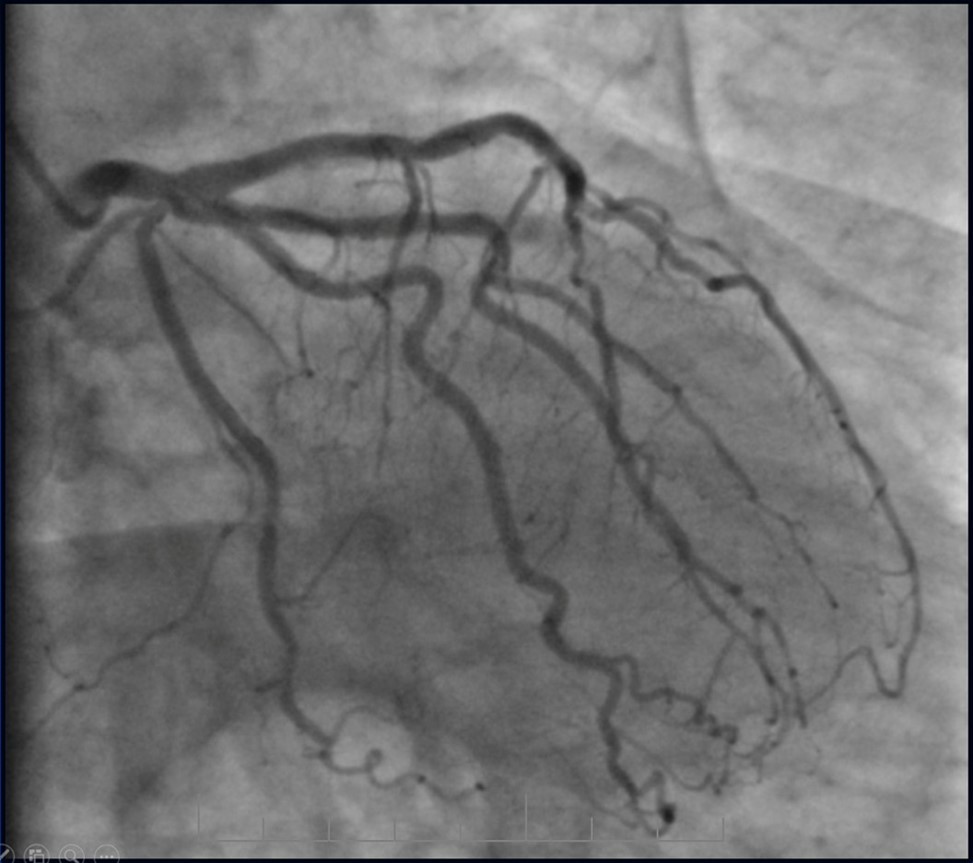

Angiography revealed rare anatomical variation LMCA quadrifurcation (Figure 1, Figure 2), 50% stenosis of the distal part of the LMCA, 40% stenosis of the ostial segment of left anterior descending (LAD) artery and diffuse prolonged 70-75-95% stenosis in mid-segment (Figure 3), 75% stenosis of the ostial segment of the circumflex (CX) artery, 75% stenosis of the ostial segment of the first marginal branch (OM1), 75-90% stenosis of the proximal segment of the intermediate artery (IMA), prolonged diffuse severe 90-95% stenosis of mid-segment of the right coronary artery (RCA) (Figure 4).

Figure 1.Quadrifurcation of the left main coronary artery

Figure 14.Left coronary artery, follow-up CAG eight months after last PCI.